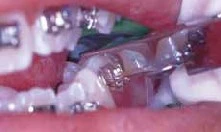

Đặc biệt chú ý mối tương quan giữa răng hàm lớn thứ nhất hàm dưới và răng hàm nhỏ thứ hai hàm dưới. Đây là tương quan khó khăn nhất trong chỉnh nha. Cần đặc biệt chu ý khi đặt mắc cài trên răng hàm nhỏ thứ 2, bởi vì nó nằm phía sau, dễ bị nhiễm nước bọt. Lỗi hay gặp là đặt khâu răng hàm lớn xuống quá thấp ở phía gần, nên chú ý tránh điều này (Hình 12a, 12b).

Hình 12a. Lỗi đặt khâu xuống quá thấp ở phía gần

Hình 12b. Đặt khâu song song mặt nhai.

Khi đặt khâu răng cối lớn thứ nhất cần thận trọng để tránh xoay quá nhiều về phía gần. Vị trí đúng là giữa rãnh giữa ngoài.

Hình 13. Ống răng hàm lớn dưới nên nằm giữa rãnh giữa ngoài theo chiều gần-xa.